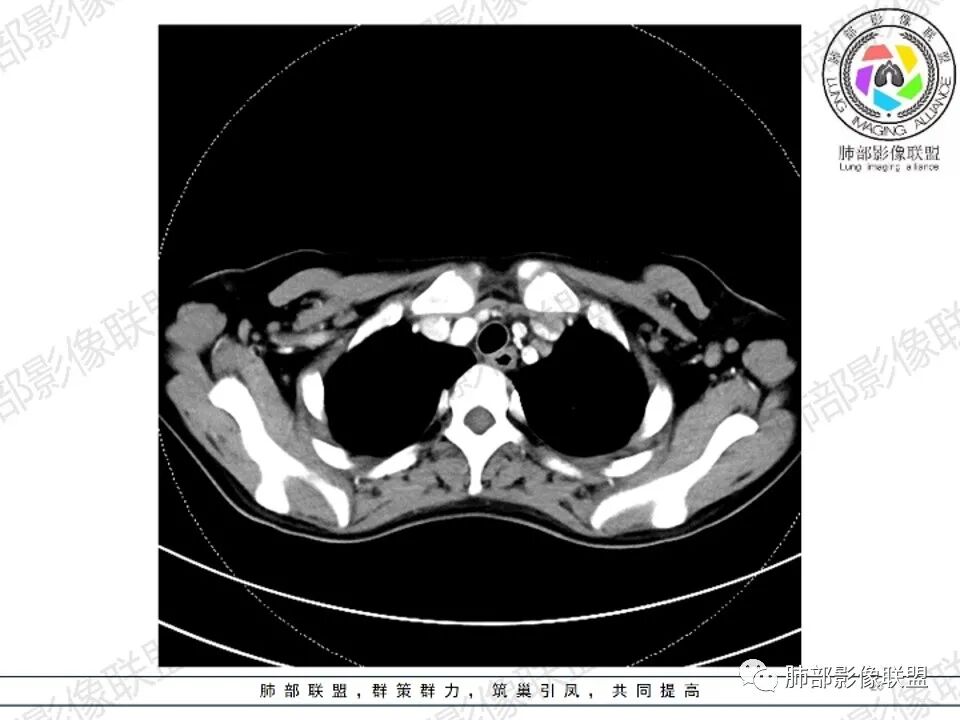

2.影像显示前纵隔不规则块状影,依势贴附心脏大血管旁,密度不均,边界不甚清楚,有结节融合感。

3.病灶轻度不均匀强化,可见血管穿行,散在液性低密度区。

双肺门未见肿大淋巴结。

4.双侧腋窝区见增大淋巴结,边界清楚。

1.年轻女性,前纵隔不规则块状影,密度不均,边界不甚清楚,有结节融合感,轻度不均匀强化,可见血管穿行,最常见最符合的无疑是淋巴瘤!